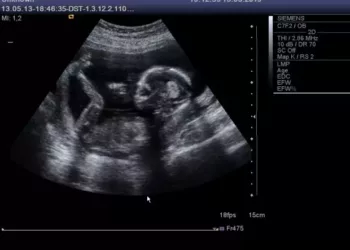

Gaby Rodriguez are doar 17 ani dar deja și-a șocat toți prietenii și familia când a spus tuturor că este...